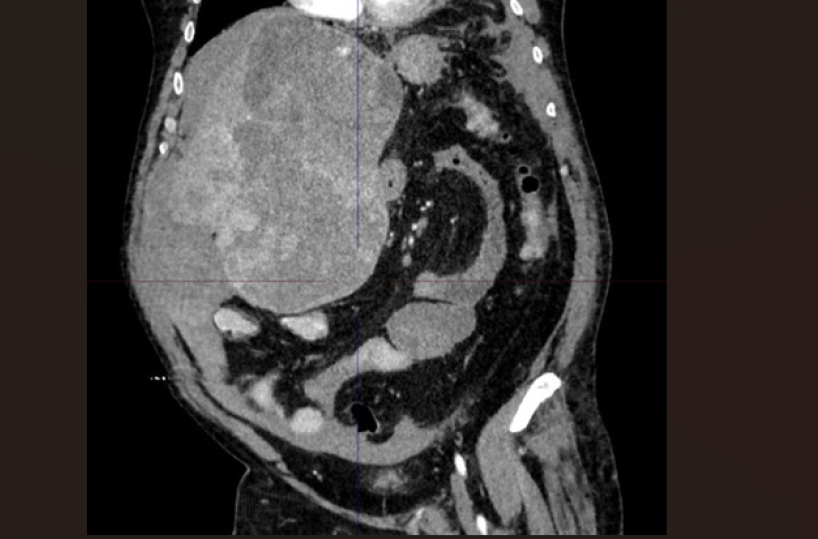

BARI - Chirurgia epatica estrema al Policlinico di Bari per l’asportazione di un tumore di quasi 5 kg e 30 cm di diametro, che occupava più della metà dell’addome in un paziente di 60 anni. Un caso di estrema complessità, giunto in urgenza con un’emorragia epatica in atto, che ha richiesto il coinvolgimento di equipe multidisciplinari per salvare la vita del paziente.

Una volta stabilizzato è stato possibile eseguire l’epatectomia sinistra allargata, intervento chirurgico eseguito dall’equipe del prof. Testini, primo operatore il dottor Panzera con la dott.ssa Arianna Pontrelli, per asportare la grossa massa tumorale e parte del fegato.